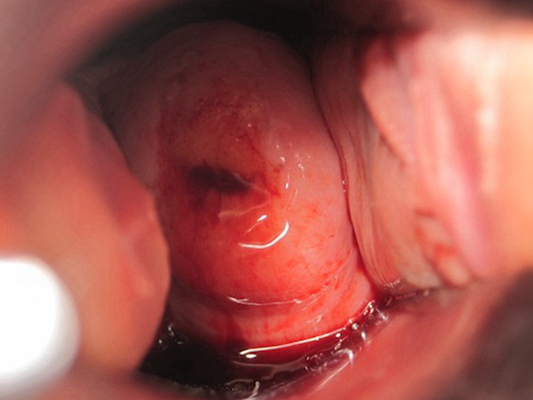

子宮肥大圖片

子宮肥大圖 (8)